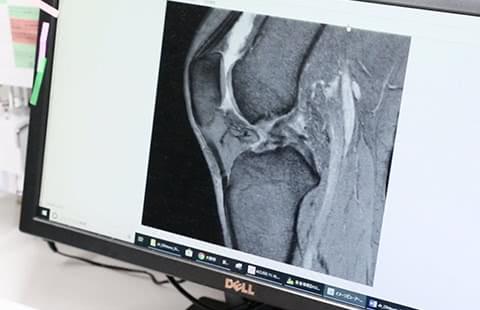

- ひざを中心とした治療経験

再生医療の道を選ぶ契機となったのは、前職で難渋する症例にPRP療法を用いたことだった。良好な結果を目の当たりにしたことで、再生医療という新たな選択肢に無限の可能性を見出し、当院へ入職。難しい病態でも画一的な治療に終始するのではなく、患者一人ひとりに合った選択肢を考え抜いて提供することを目指してきた。治療後も常に患者へ寄り添い続けるような医師像を理想とする。

再生医療の道を選んだ理由スポーツ障害の治療を多く行っていた前職、ジャンパー膝とも呼ばれる膝蓋靭帯炎(しつがいじんたいえん)に苦しむスポーツ選手を治療したときのことです。その選手は1年近く保存療法を行ってきましたが効果は薄く、ひざの状態も良いとは言えませんでした。そんなときに再生医療のPRP療法を用いて治療を行うと、痛みを改善する効果が見られたのです。

このようなケースを何度も経験し、早い段階でひざの痛みを改善するために再生医療が有効な手だてになる、と強く感じました。漫然と治療を続けてひざの状態が悪化し「手術しか残されていない」という事態になることを未然に防ぐ意味でも、新たな選択肢である再生医療を多くの人に知っていただきたいです。